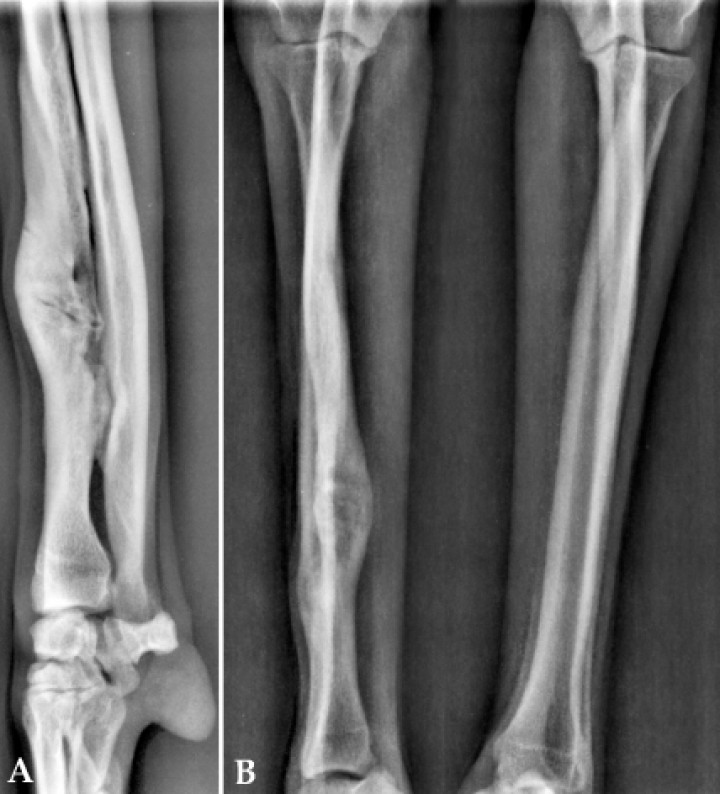

Por último, acudió a revisión un mes después (3 meses desde el diagnóstico de no unión hipertrófica) sin muestras evidentes de alteración de la marcha, sin dolor y con una exploración clínica dentro de los parámetros normales, apreciándose únicamente un ligero abultamiento en la zona del foco de fractura y la rigidez articular del carpo. En la radiografía se observó una unión clínica y remodelación del foco de fractura (Fig. 5). En este momento se decidió dar de alta al paciente.

<p>(<strong>A</strong>) Proyección mediolateral. (<strong>B</strong>) Proyección craneocaudal. Detalle de la consolidación de la fractura un mes después de la última sesión de ondas de choque (día 604).</p>

(A) Proyección mediolateral. (B) Proyección craneocaudal. Detalle de la consolidación de la fractura un mes después de la última sesión de ondas de choque (día 604).